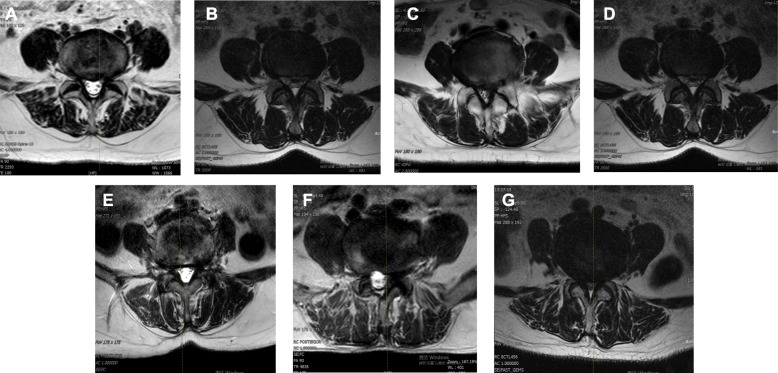

Fig. 2.

Representatives of MRI of each group of DLSS cases. A Control group, normal; B DLSS Group 6, ACD > 500 m; C DLSS Group 5, 400 m < ACD ≤ 500 m; D DLSS Group 4, 300 m < ACD ≤ 400 m; E DLSS Group 3, 200 m < ACD ≤ 300 m; F DLSS Group 5, 100 m < ACD ≤ 200 m; G DLSS Group 6, ACD ≤ 100 m